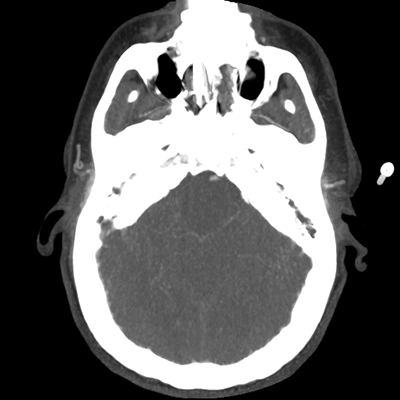

The patient goes down to CT. The following images are obtained. The subdural fluid collection is stable, as is the ventricular caliber.

NCHCT

Starting with the non-contrast head CT, we can appreciate that there's actually not much residual subarachnoid blood at all; it's essentially all resorbed already (and cleared through the EVD). The ventricular caliber is stable. With the CTA head (for convenience's sake, the MIPs were shown), it's subtle, but we can see that the PCAs on each side are not as smooth and regular. The right MCA, starting at the bifurcation, also becomes narrower. This is [radiographic] vasospasm. Now, looking at the CT perfusion-- specifically, the Tmax (MTT) map that were selected-- there's clearly some abnormality within the bilateral cerebellar hemispheres and occipital lobes. Not a lot, but it's there. Delving further into this map, we can appreciate that the areas of abnormality are mainly green, signifying that these areas have Tmax > 6 seconds. This is the threshold that is specific, not sensitive, for vasospasm.